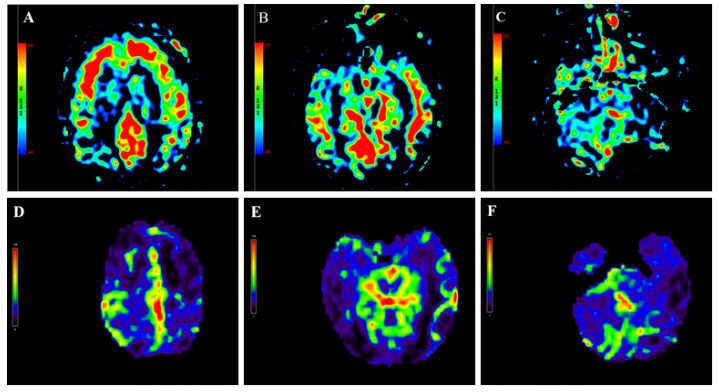

| 注:(A-C)中毒第9天,头颅ASL显示双侧额叶、颞叶皮层下白质区对称性灌注增高,双侧小脑半球灌注减低;(D-F)中毒后第6月头颅ASL显示双侧额叶、枕叶、小脑半球灌注弥漫性减低;图中红色代表高灌注,蓝色代表低灌注,黄色代表两者之间 图 2 本例患者头颅ASL灌注成像动态变化 |

目前关于中毒性脑病局部脑血流变化的研究较少,本例患者进行了脑灌注检查,以期为中毒性脑病提供更多具有特征性的诊断依据。有研究[12]对3例甲苯中毒性脑病患者进行了磁共振ASL检测,结果发现中毒组所有感兴趣区平均脑血流量值和正常对照组无差异。然而,川玲等[11]通过核素脑血流灌注显像的方法对46例中毒性脑病患者进行观察,发现大部分患者存在不同程度的局限性或弥漫性脑血流灌注减低。本例哒螨灵中毒患者磁共振ASL检测显示急性期不同部位脑血流变化趋势不一,表现为双侧额颞叶皮层下白质区对称性高灌注,基底节、小脑、枕顶叶对称性低灌注,6个月后复查发现全脑多部位呈弥漫性低灌注。通常,中毒性脑病伴随脑细胞水肿和血管内皮细胞肿胀,影响脑的血液循环,导致低灌注。本例中毒性脑病急性期部分脑白质区呈现高灌注,其原因尚不明确,可能与中毒后这些区域脑实质发生充血肿胀、血流速度增快有关[13]。